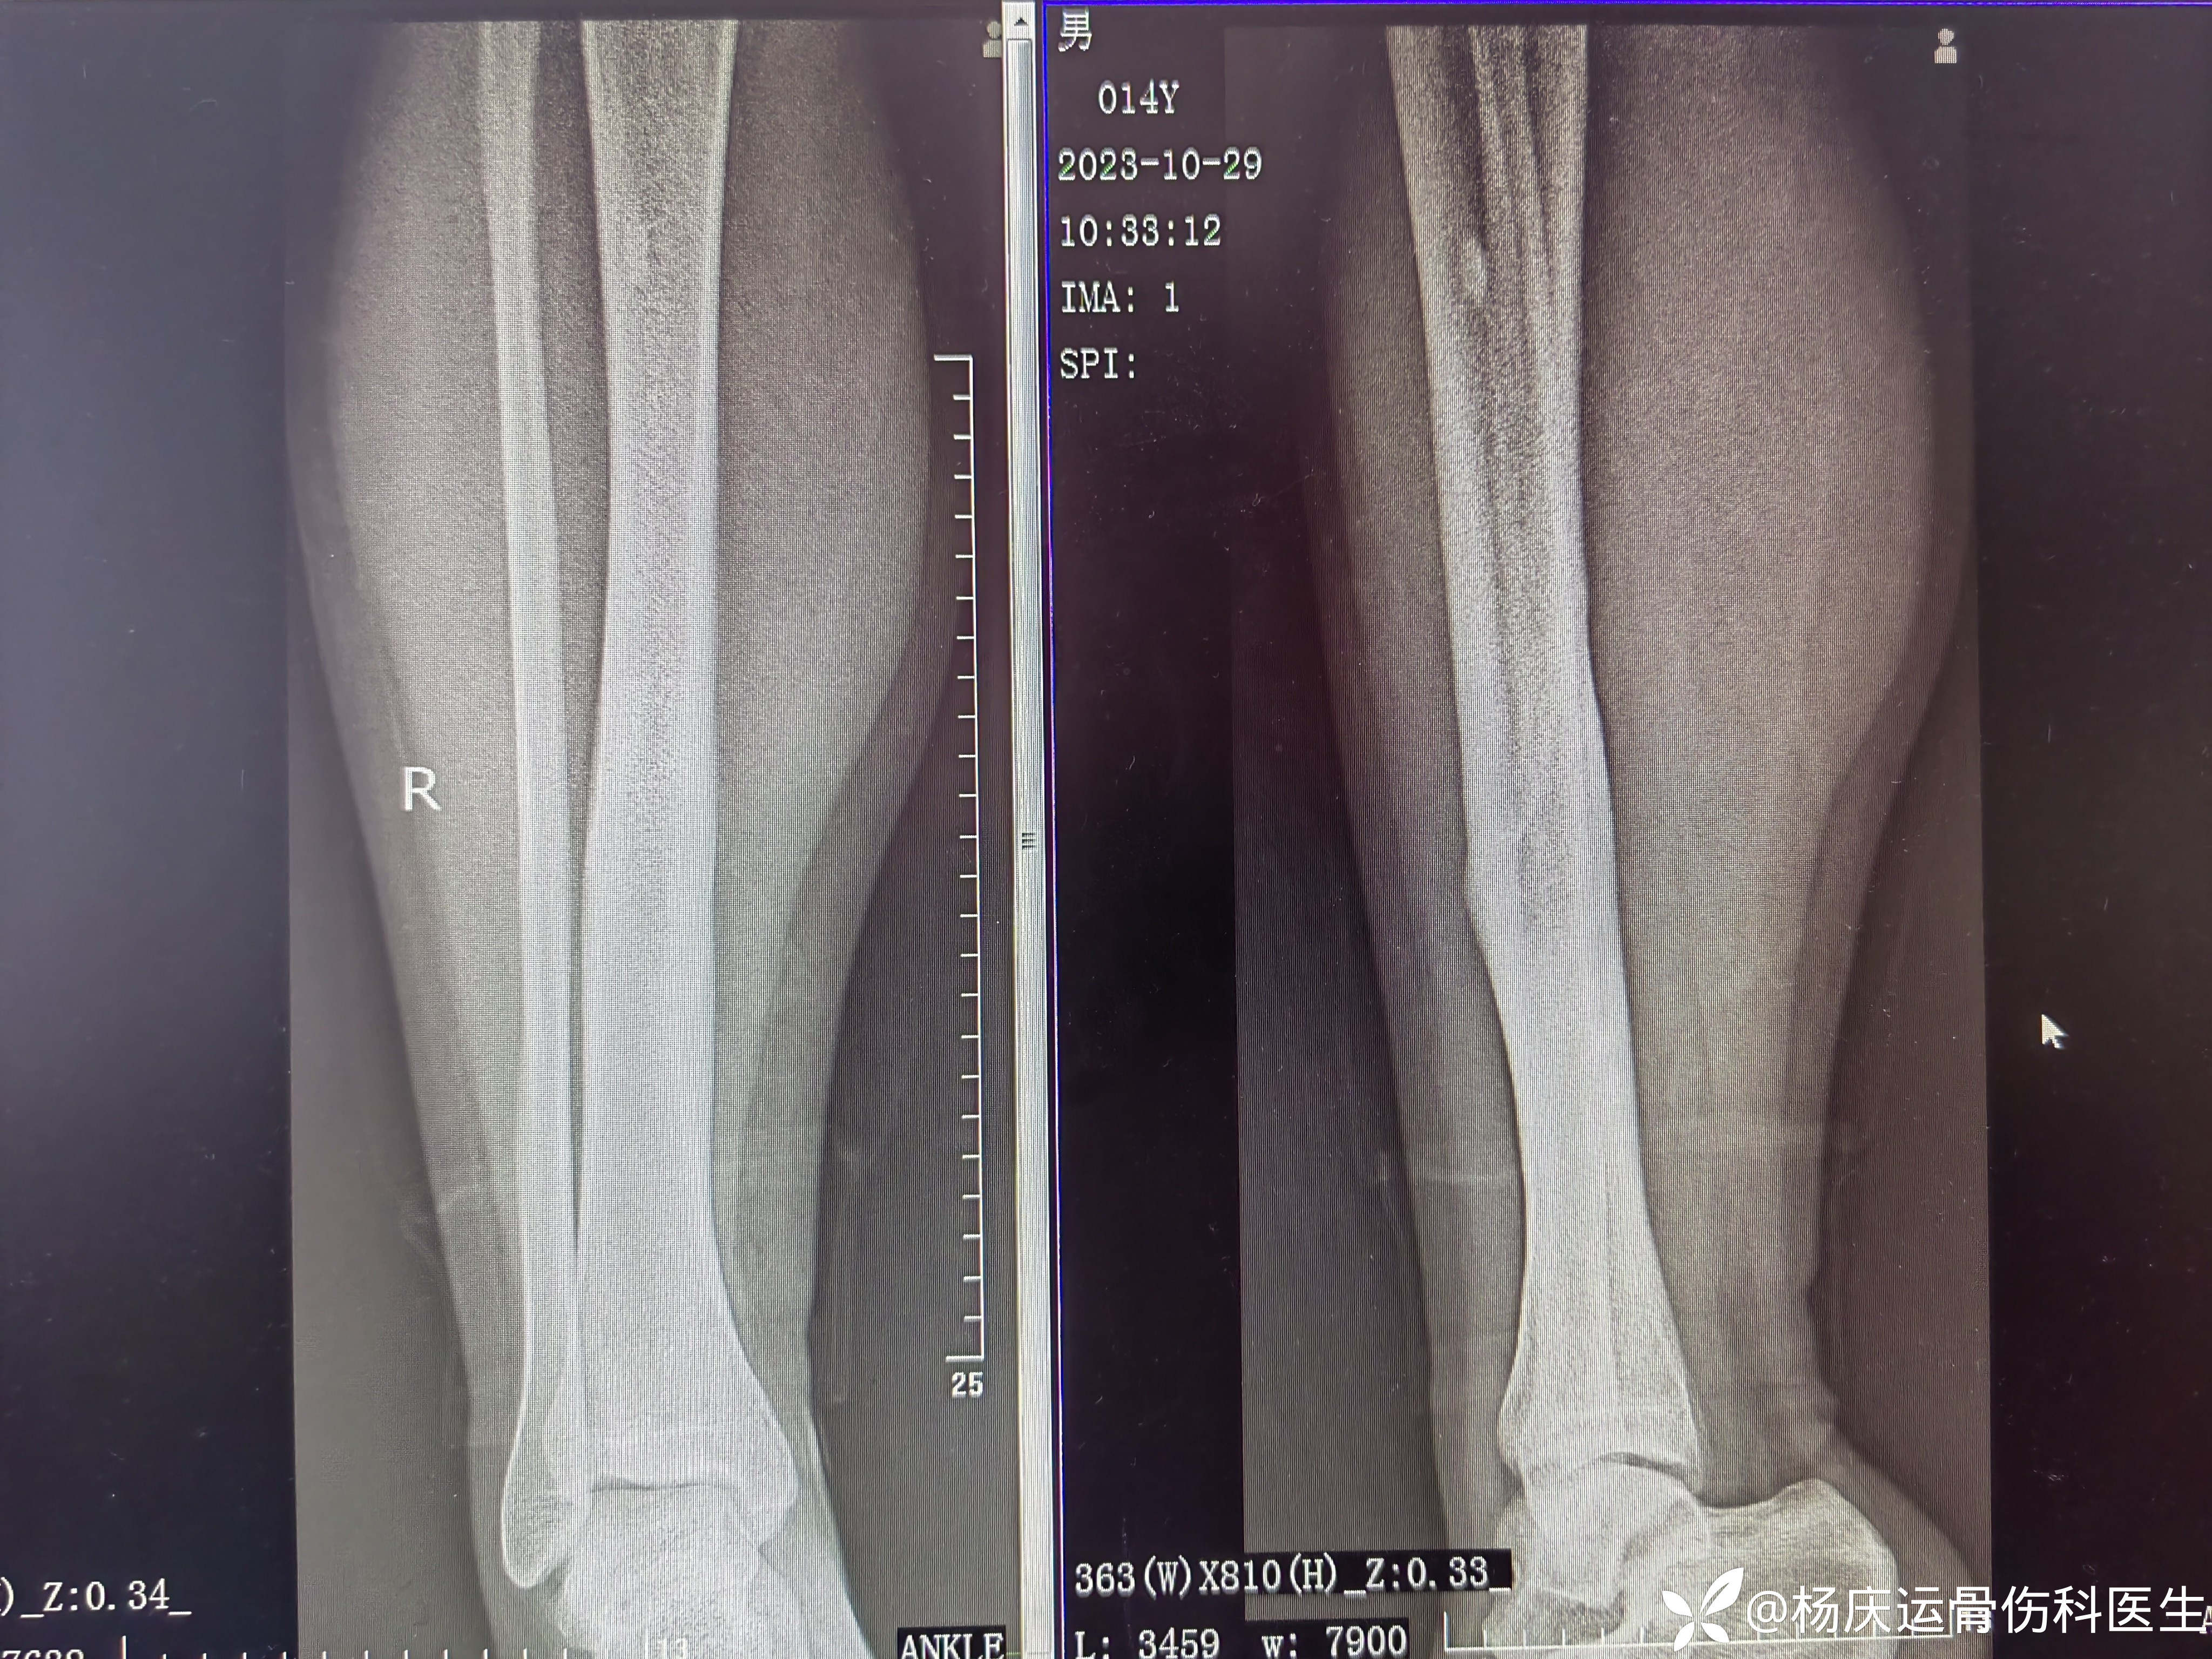

曹谦湘潭市中医院 等 4 位达人已点赞患者马,男,14岁,“右小腿外伤肿痛活动受限1天”于2013-2-13入院。

身高:173cm,体重:85kg

初步诊断:右胫骨中下1/3段骨折

治疗方案:闭合复位夹板外固定治疗

首诊片